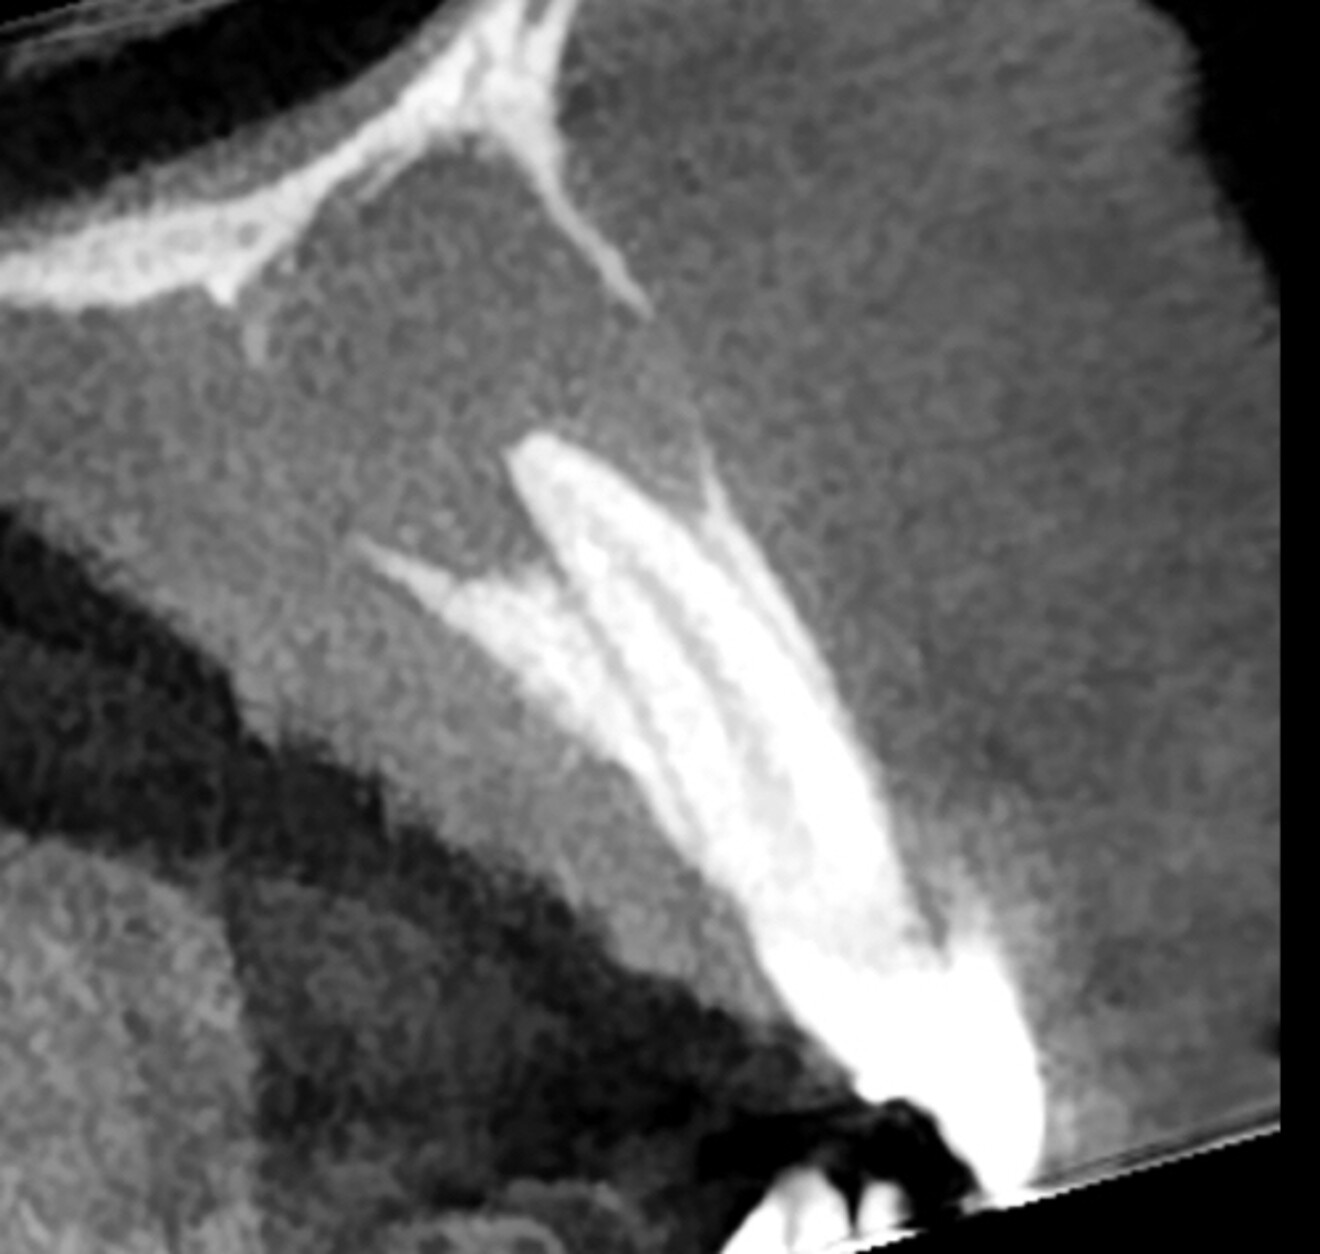

The patient presented for assessment of a fistula in the anterior maxilla on a radiograph, appearing as a large lesion above the lateral incisor (Fig. 1). The patient recalled having been hit by a ball a long time before. A CBCT scan was taken, and it showed a large cystic lesion destroying a large portion of the anterior maxilla. Owing to the edge-enhancing capability of the DTX software provided by artificial intelligence, we can enhance the quality of the image. Since the CBCT scan was taken in a different centre, we imported the DICOM file into the DTX software. The image clearly showed the nerve entering the central incisor and a thin layer of bone covering the apex, and the nerve and periodontal ligament in this area were intact (Fig. 2).

Fig. 2a: CBCT images showing the size of the lesion and destruction of both cortical walls. Artificial intelligence-enhanced image.